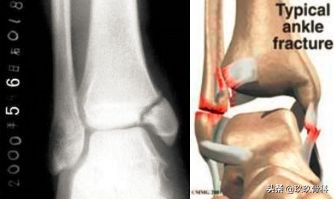

踝的骨折▲▲▲

辅助检查

- X线 踝关节正侧位(必要时应加照踝穴位)

- 内外踝骨折